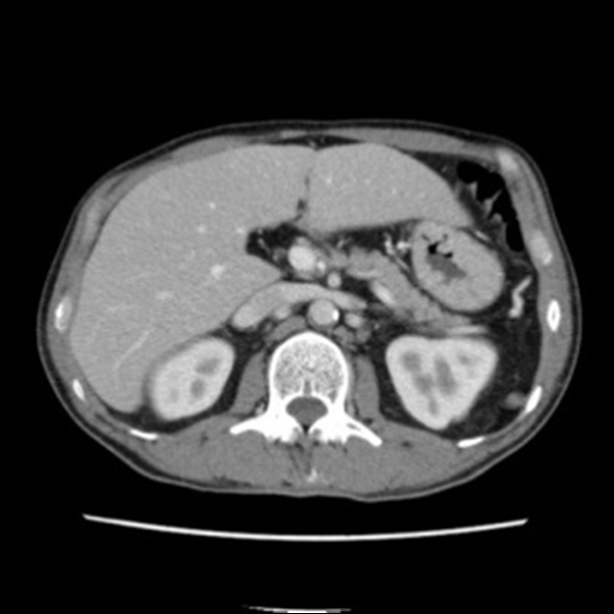

腹部CT

肝臓や膵臓や腎臓、腸などの腹部病変、突然の腹痛、腸閉塞などの消化管が原因の疾患、癌などの病気を見つけることができます。

造影CT

造影剤という薬を注射して撮影を行います。撮影する部位や方法の違いで、何回か撮影することがあります。痛みの原因を調べたり、腫瘍が良性か悪性かの精査、血管の狭窄や動脈瘤を見つけることができます。造影剤が入ると血管や腫瘍などがはっきりと写るようになります。 手術前の評価にも使用します。